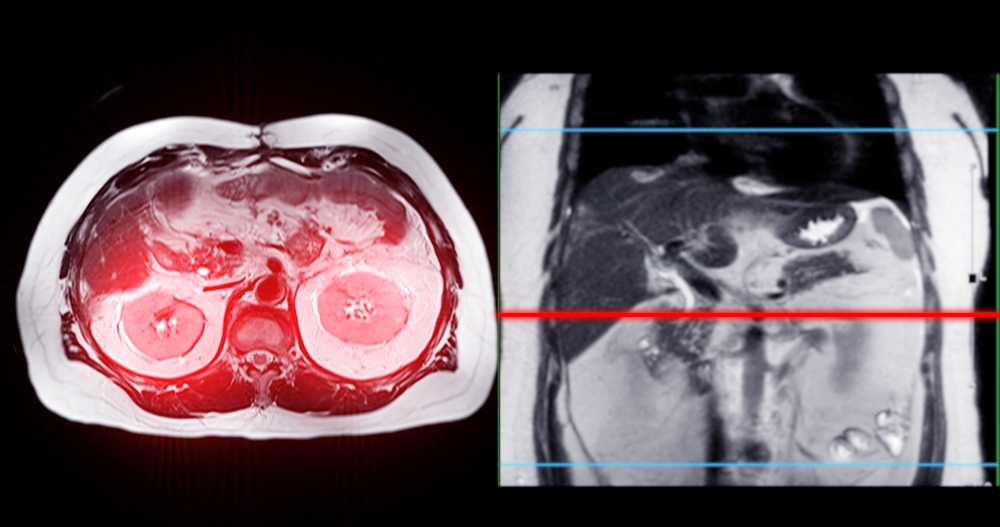

• Magnetinio rezonanso tomografija (MRT) – aiškiai matomi navikai smegenyse ar pilvo srityje.